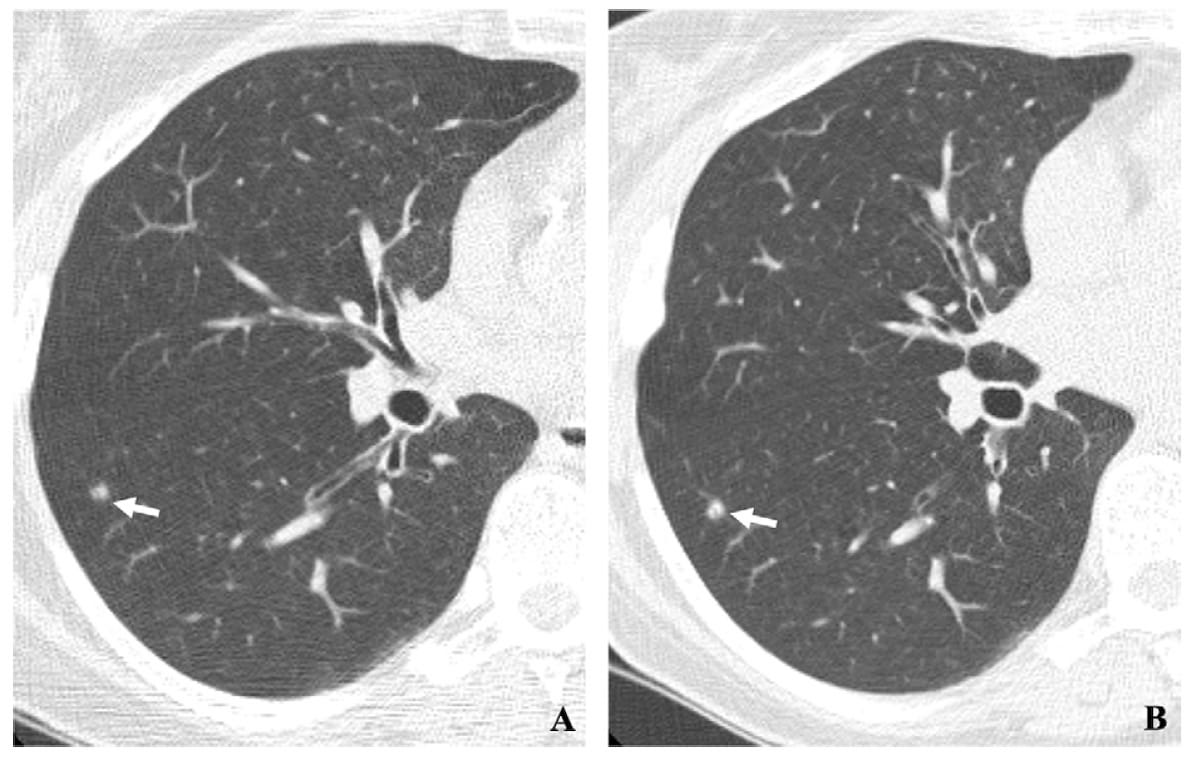

Дифференциальная диагностика заболеваний плевры